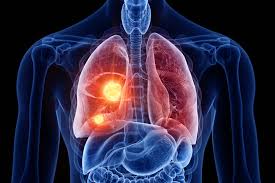

Moreover, the discoloring of the lining of the mouth may also be a sign of cancer. However, the contents and opinions expressed in 12healthy are not meant to replace the opinion and treatment options from a professional. Basically this type of cancer is highly invasive to bone (in most cases the jaw bone). Typically, a blood clot forms over your empty socket. Cancer that has started in one place can spread to and invade other parts of the body. Mouth cancer on your gums can sometimes be mistaken for gingivitis, a common gum inflammation. When cancer spreads to the bones. It may be numb or firm to feel and doesn't fade away over time. Treatment for dog mouth cancer. These cancers usually occur in the thin, flat cells called squamous cells that line the buccal mucosa and other parts of the mouth. Cancer in the jaw often spreads there from other areas of the mouth or throat. Often, by the time a patient sees a doctor for a diagnosis, the tumor has grown into the neck. Lumps on the roof of your mouth or along your gumline may be the only jaw cancer symptoms you experience.

It may be numb or firm to feel and doesn't fade away over time. Leukoplakia (white and hardened patches) squamous cells is the name given to the flat cells that are present on the surface of the tongue, mouth and lips. Although many jaw growths are benign, they can still do plenty of harm. A white or red patch on the gums, tongue, tonsil, or lining of the mouth. This aggressive type of cancer is more likely to spread to the lymph nodes Oral complications affect the mouth. These cancers usually occur in the thin, flat cells called squamous cells that line the buccal mucosa and other parts of the mouth. Symptoms are similar to more typical osteosarcomas except that they may occur in very young children and are more widespread. Lumps on the roof of your mouth or along your gumline may be the only jaw cancer symptoms you experience. If a tumor spreads to the bone, it's called bone metastasis. Ewing sarcoma also is more likely to be in kids and young. What does a dry socket look like? Osteosarcoma, the most common bone cancer, usually happens to people ages 10 to 30 and most often starts in the arms, legs, or pelvis.

6 Signs You Might Have Mouth Cancer from hips.hearstapps.com Buccal mucosa is another name for the inside lining of the cheeks. Taken by mouth or injection, they attack any cancer cells in the body. If a tumor spreads to the bone, it's called bone metastasis. Mouth cancer on your gums can sometimes be mistaken for gingivitis, a common gum inflammation. When cancer spreads to the bones. These cells are the most common grounds for mouth cancers. If the tumor is small, the excised area can be closed after surgery. A white or red patch on the gums, tongue, tonsil, or lining of the mouth.